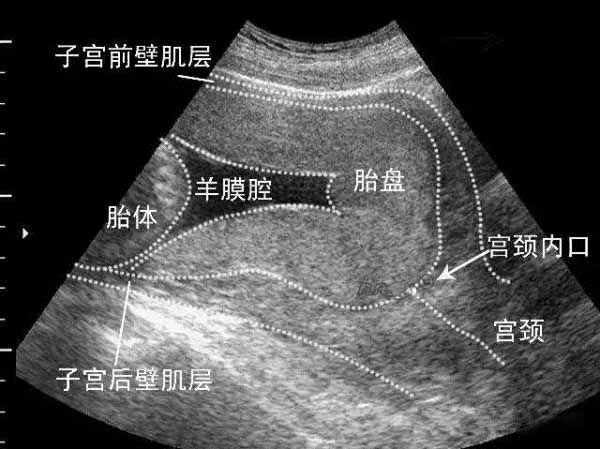

图1. 人类子宫中的胎盘丨来源:维基百科